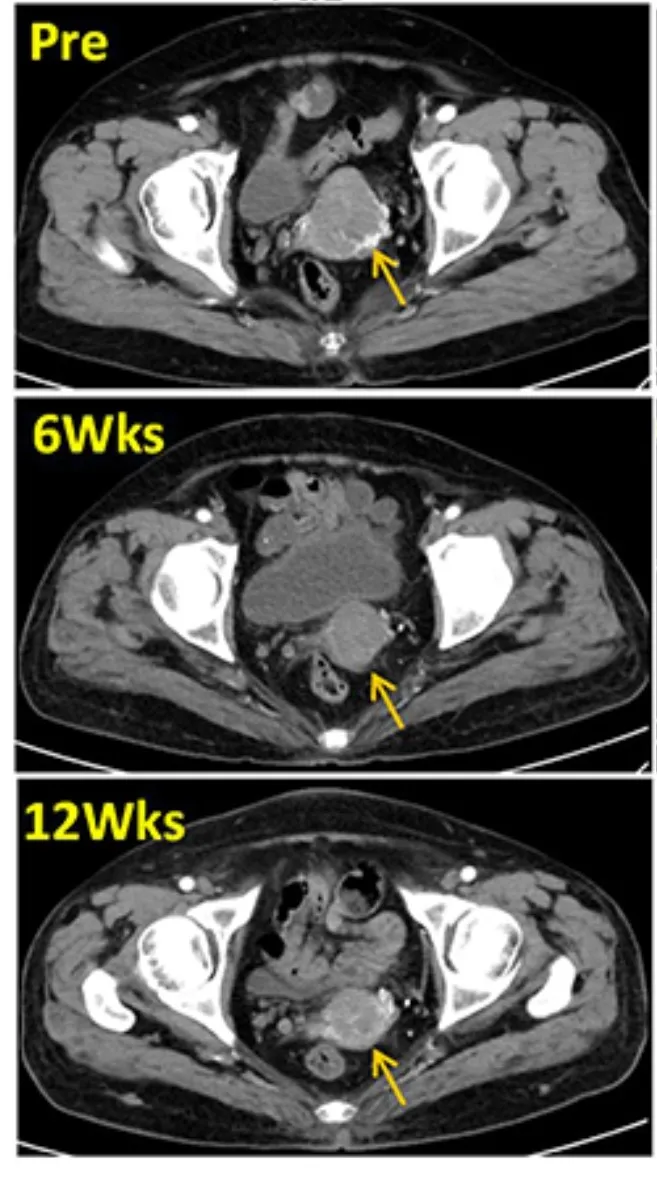

3、增强盆腔CT:患者在回输TIL前、治疗后6周、治疗后12周时,增强盆腔CT扫描目标病灶分别为4.9cm、3.3cm、3.0cm。显然,回输TIL细胞后,患者的肿瘤病灶迅速缩小(详见图1)。

图1 TIL治疗前后,盆腔增强CT对比

22个月后,影像检查显示(黄色箭头)肿瘤消失得无影无踪